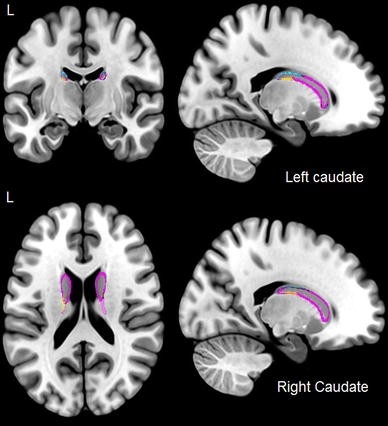

Рис. 25 Эффект билингвизма на хвостатое ядро с двух сторон в группе билингвов с ограниченным языковым погружением. Увеличения показаны жёлтым цветом, а сокращения – синим. (Из: Pliatsikas C., DeLuca V., Moschopoulou E. & Saddy J.D. (2017). Immersive bilingualism reshapes the core of the brain. Brain Structure and Function, 222(4), 1785–1795. https://doi.org/10.1007/s00429-016-1307-9 Creative Commons Attribution 4.0 International License)